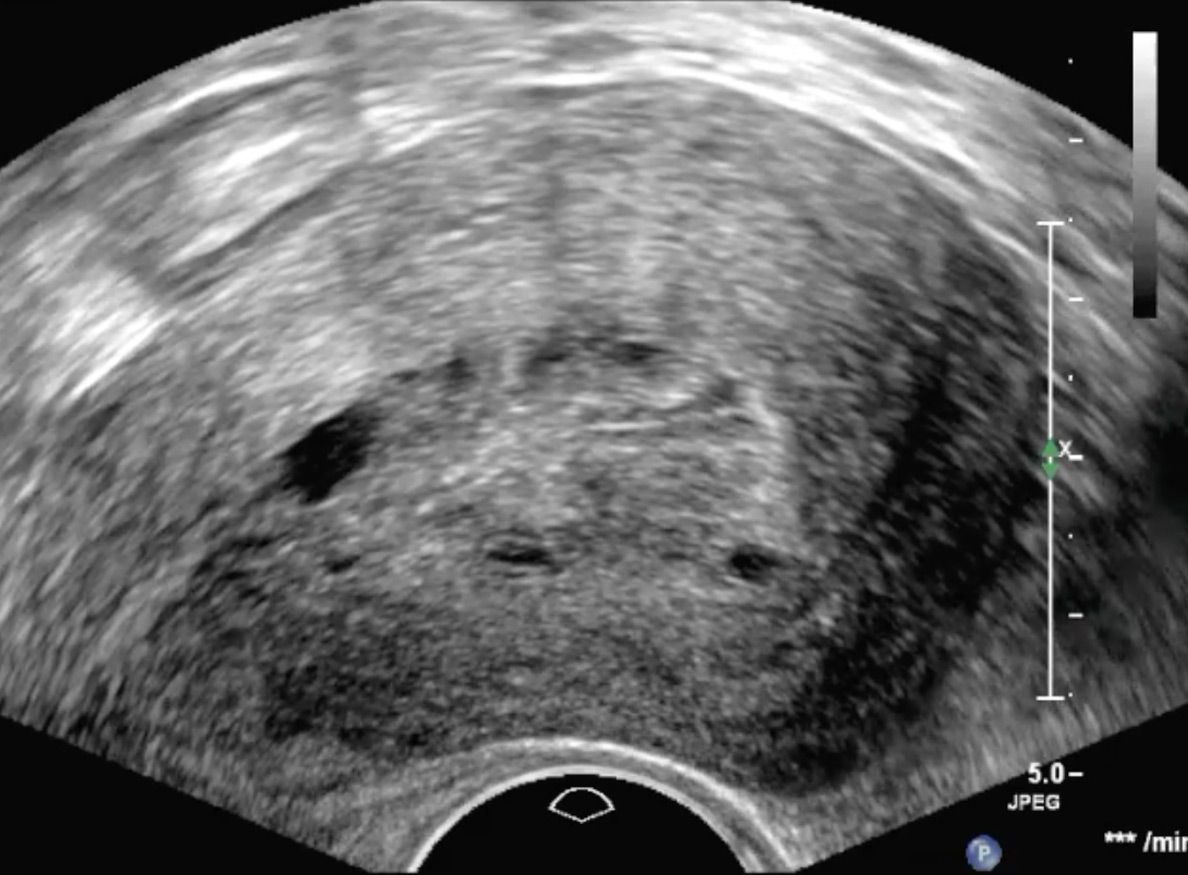

Adenomyosis

Die Endometriose ist eine Erkrankung, die durch Auftreten von Gebärmutterschleimhaut-ähnlichem Gewebe außerhalb der Gebärmutterhöhle  geprägt ist. Das abnorm lokalisierte Gewebe kann ein Vielfalt an Symptomen auslösen. Von zyklusabhängigen Schmerzen, Blutungsunregelmäßigkeiten bis hin zum unerfüllten Kinderwunsch können diese Probleme reichen.

Aufgrund der Vielfalt an möglichen Symptomen handelt es sich in der Differentialdiagnostik um ein Chamäleon. Insbesondere die Manifestation innerhalb des Eierstocks (Endometriome, Schokoladenzysten) oder innerhalb der Gebärmuttermuskulatur  weisen ein charakteristisches Ultraschallbild auf. Daher ist die Vaginalsonographie ein wichtiger Bestandteil der Diagnostik zur Erkennung der Endometriose.